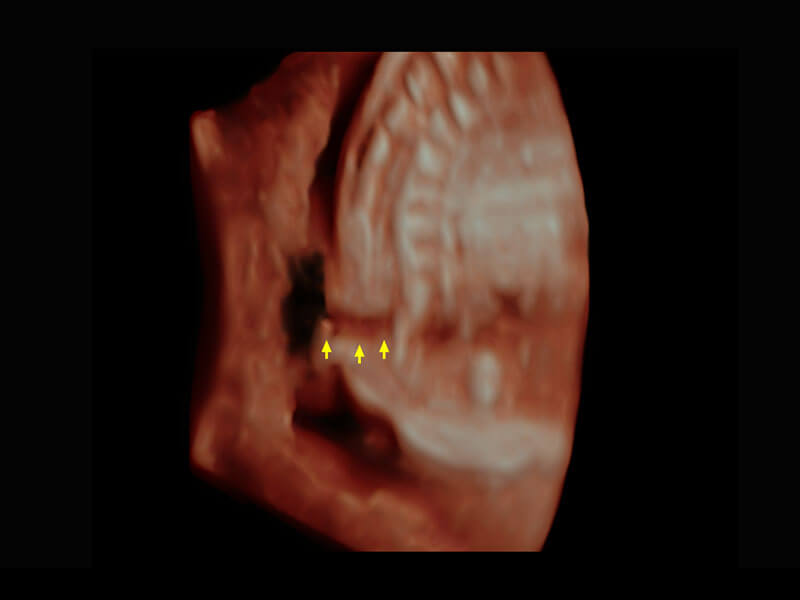

P60搭载一系列胎儿心脏成像技术,实现精细的胎儿心脏评估。

• 四腔切面

• 四腔心血流

• 右室双出口

• 胎心容积成像